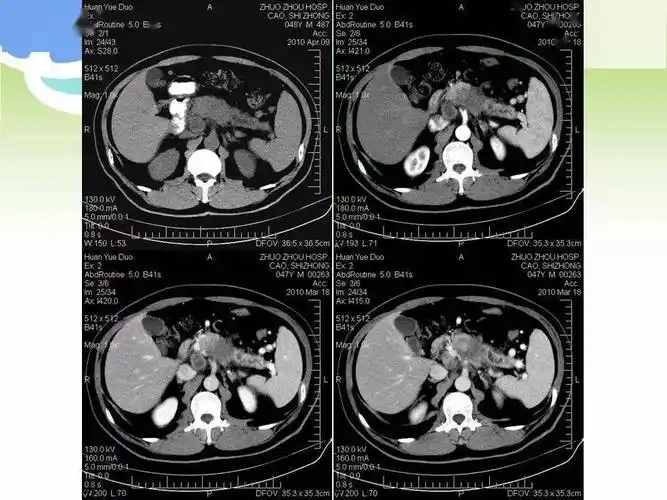

胰腺癌的影像诊断